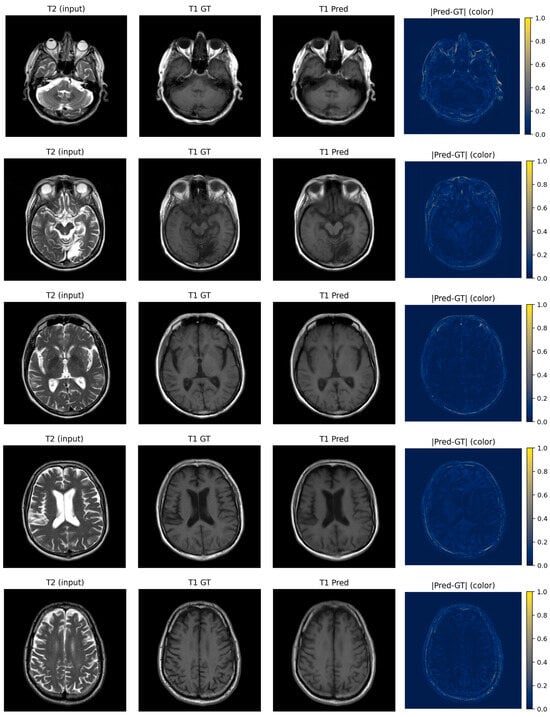

Bidirectional T1–T2 Brain MRI Synthesis Using a Fusion U-Net Transformer for Real-World Clinical Data

Obtaining multiple MRI contrasts for each patient prolongs scan acquisition time, increases healthcare costs, and may not always be feasible due to patient specific constraints. Deep learning-based MRI contrast synthesis offers a potential solution, yet most existing approaches are evaluated on preprocessed public benchmarks that do not reflect real-world clinical variability. In this study, we propose a fusion U-Net transformer framework for bidirectional T1-weighted ↔ T2-weighted brain MRI synthesis trained and evaluated exclusively on retrospectively acquired clinical data. The proposed architecture integrates multiscale convolutional feature extraction with axial attention mechanisms and a transformer bottleneck for efficient global context modeling. A fusion refinement block is incorporated to mitigate skip connection artifacts. An adversarial training strategy with the least squares GAN objective and a hybrid loss combining L1 reconstruction and structural similarity (SSIM) is employed to promote both pixel-level accuracy and perceptual fidelity. The model is evaluated using SSIM and PSNR metrics alongside qualitative expert assessment conducted by two board-certified radiologists. For both synthesis directions, the framework achieves competitive quantitative performance against baseline models under the challenging conditions of clinical data. Expert evaluation confirms high anatomical fidelity and clinically acceptable image quality across both synthesis directions. These results indicate that the proposed framework represents a promising approach for multi-contrast MRI synthesis in clinically heterogeneous data environments. Full article

Figure 1